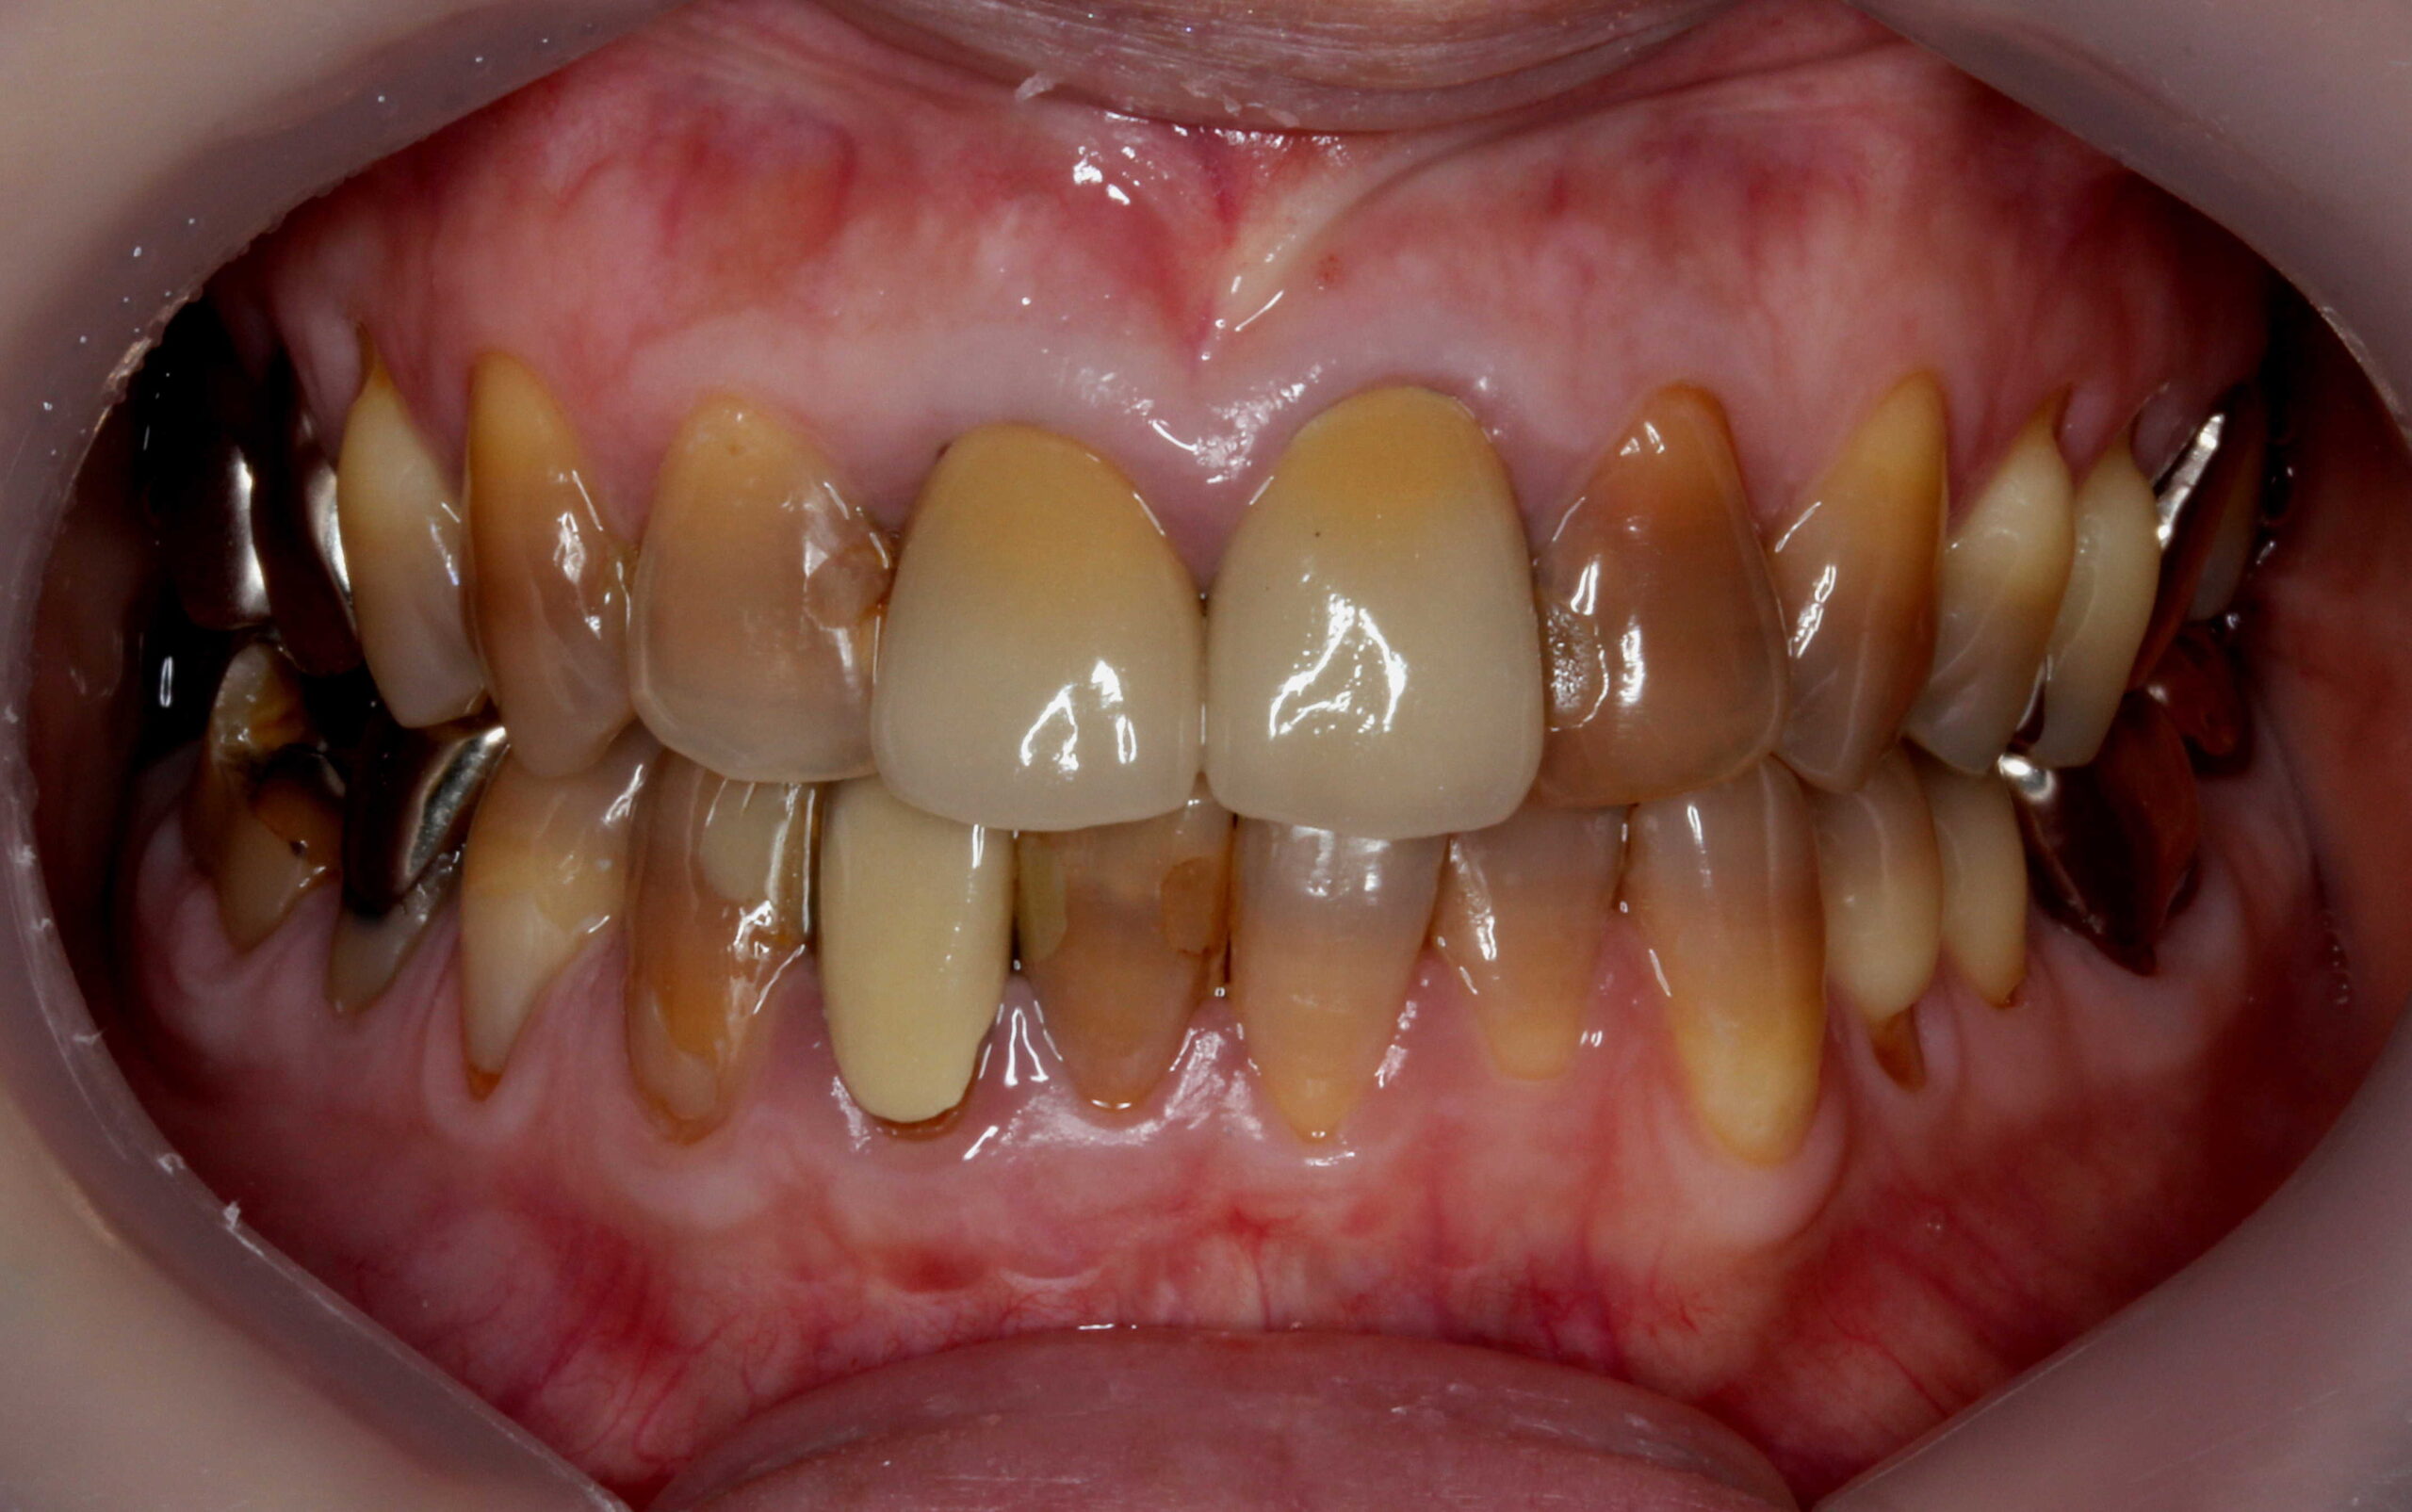

他院にてテトラサイクリン歯を上前歯6本のセラミッククラウンで被せてある症例です。

従来のクラウンの方法では支台になる歯の外周を大きく削ることになってしまいます。

当院でも以前はこのような方法で多くの審美歯科を行っていました。

他院では前歯6本を削ってクラウンで治しています。

患者様は削らない方法で審美的に揃えたいということでご来院されました。

奥の右上54、左上45も削らずに前歯と審美的に揃えたいということで、当院で削らないラミネートベニアで治しました。

上下の色の差を改善するために下の前歯の希望されていましたが、咬み合わせで破折してしまうので下の前歯は削らないラミネートベニアを含むベニア治療ができません。

テトラサイクリン歯はホワイトニングがききで一定の効果を期待できるので、下の前歯には当院でホワイトニングをしました。

「削らないでキレイになって嬉しい!」と患者様にも喜んで頂けました。